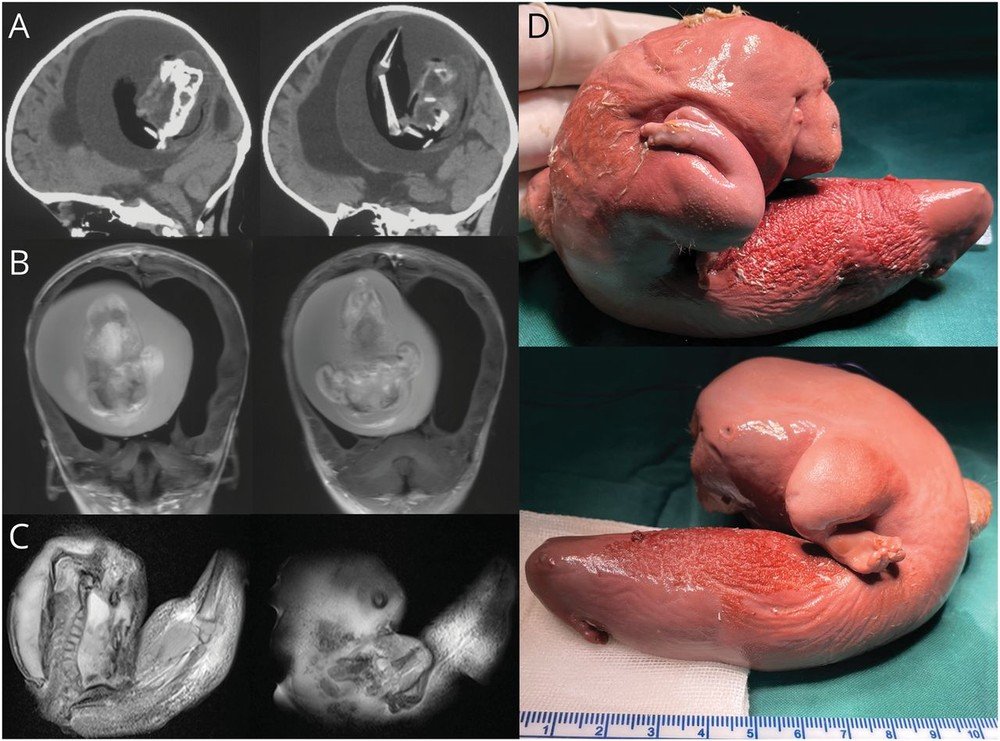

Médicos da Universidade Fudan, que fica na China, retiraram um feto “gêmeo” do cérebro de uma menina de 1 ano, em Shangai. A anomalia foi publicada na revista científica Neurology.

A menina enfrentava forte “atraso motor e perímetro cefálico aumentado”, o que a levou para exames. A cirurgia deu aos médicos a chance de fazer o mapeamento. que mostrou “variantes idênticas de nucleotídeo único na criança e no feto”. Segundo os médicos, o “gêmeo” é um “feto in feto intracraniano”, devido a blastocistos não separados. Um parasita.

É uma condição rara. Estima-se que ela possa afetar 1 a cada 500 mil fetos vivos. Apesar disso, são 200 casos registrados na história.